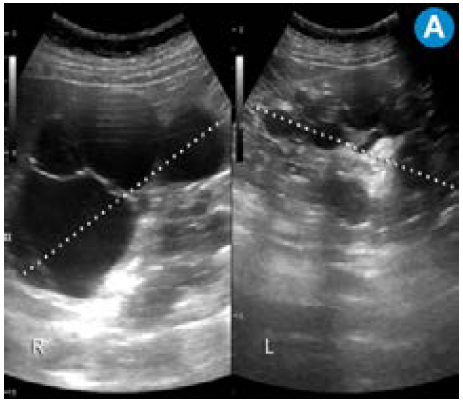

El diagnóstico de la ADPKD en un individuo con historia familiar positiva se basa en las imágenes diagnósticas (figura 1), aunque también se debe tener en cuenta la historia clínica, los antecedentes familiares, los signos y los síntomas. Para el diagnóstico de la PKD, se requiere la presencia de múltiples quistes renales (tabla 1). El número de quistes necesarios para el diagnóstico se correlaciona con la edad del paciente.

Por su alta sensibilidad, disponibilidad y bajo costo, la ecografía renal es el estudio inicial con el que se pueden observar riñones grandes con quistes bilaterales, múltiples y tamaño variable (figura 1); sin embargo, es altamente dependiente del operador y es menos sensible para detectar quistes <1cm que se visualizan mejor en la escanografía o en la resonancia magnética 24. Pese a que en la actualidad no existen criterios estandarizados en estas dos técnicas imagenológicas para el diagnóstico de la PKD, la tomografía computarizada (TC) y la resonancia magnética (RM) son más sensibles para el diagnóstico de los quistes en los casos dudosos, la detección de complicaciones, la valoración de la progresión y la respuesta al tratamiento 25 (figura 2).

Los criterios ultrasonográficos para realizar el diagnóstico de la ADPKD varían según el conocimiento del genotipo familiar. En la mayoría de los casos, el individuo en riesgo pertenece a una familia en la que no es conocido el genotipo. En cuanto a los criterios ecográficos de Ravine, en la actualidad son los más aceptados para evaluar pacientes con alto riesgo de PKD1 (tabla 1); sin embargo, dado que la mutación PKD2 se asocia con enfermedades menos graves, los pacientes tienden a ser subdiagnosticados cuando se utilizan estos criterios 26. Su sensibilidad y especificidad es del 99% y del 95% en pacientes de 30 años con alto riesgo de mutación PKD1. En pacientes con riesgo de PKD2, los hallazgos por ecografía son específicos en gran medida pero la sensibilidad disminuye a 67% 26. En general, aunque los riñones no crecen a un ritmo más rápido, los pacientes con PKD1 los tienen más grandes y con mayor número de quistes en el momento del diagnóstico que los pacientes con PKD2 27-29.

En la ARPKD, el diagnóstico puede ser realizado en el período intrauterino, neonatal o en los primeros meses de vida por medio de una ecografía renal en la que se observan los riñones aumentados de tamaño, con pérdida de la relación corticomedular, hipoplasia pulmonar y oligohidramnios debido al bajo gasto urinario 31. En edades posteriores se prefieren las imágenes por TC y RM para seguimiento o, como ya se mencionó, para casos dudosos. En las fases tempranas, los riñones pueden ser de tamaño y forma normal; en las fases posteriores aumenta el número y el tamaño de los quistes, con distribución difusa del parénquima, aumento del tamaño (se alcanzan longitudes de hasta 40cm) y, por consiguiente, aumento del volumen renal. La RM es la técnica de elección empleada para la volumetría de los quistes y del parénquima como indicadores de progresión o de respuesta al tratamiento.